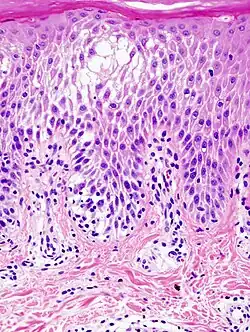

Histopathological image of dyshidrotic dermatitis, showing focal spongiotic change in the epidermis.

Spongiosis is mainly intercellular[1] edema (abnormal accumulation of fluid) in the epidermis,[2] and is characteristic of eczematous dermatitis, manifested clinically by intraepidermal vesicles (fluid-containing spaces), "juicy" papules, and/or lichenification.[3] It is a severe case of eczema that affects the epidermis, dermis or subcutaneous skin tissues.[4] The three types of spongiotic dermatitis are acute, subacute and chronic.[4] A dermatologist can diagnose acute spongiotic dermatitis by examining the skin during an office visit, but a biopsy is needed for an accurate diagnosis of the type.